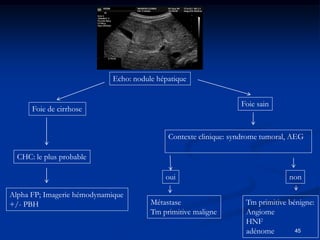

Echo: nodule hépatique

Foie sain

Foie de cirrhose

Contexte clinique: syndrome tumoral, AEG

CHC: le plus probable

oui                                 non

Alpha FP; Imagerie hémodynamique

+/- PBH                                 Métastase                  Tm primitive bénigne:

Tm primitive maligne       Angiome

HNF

adénome        45